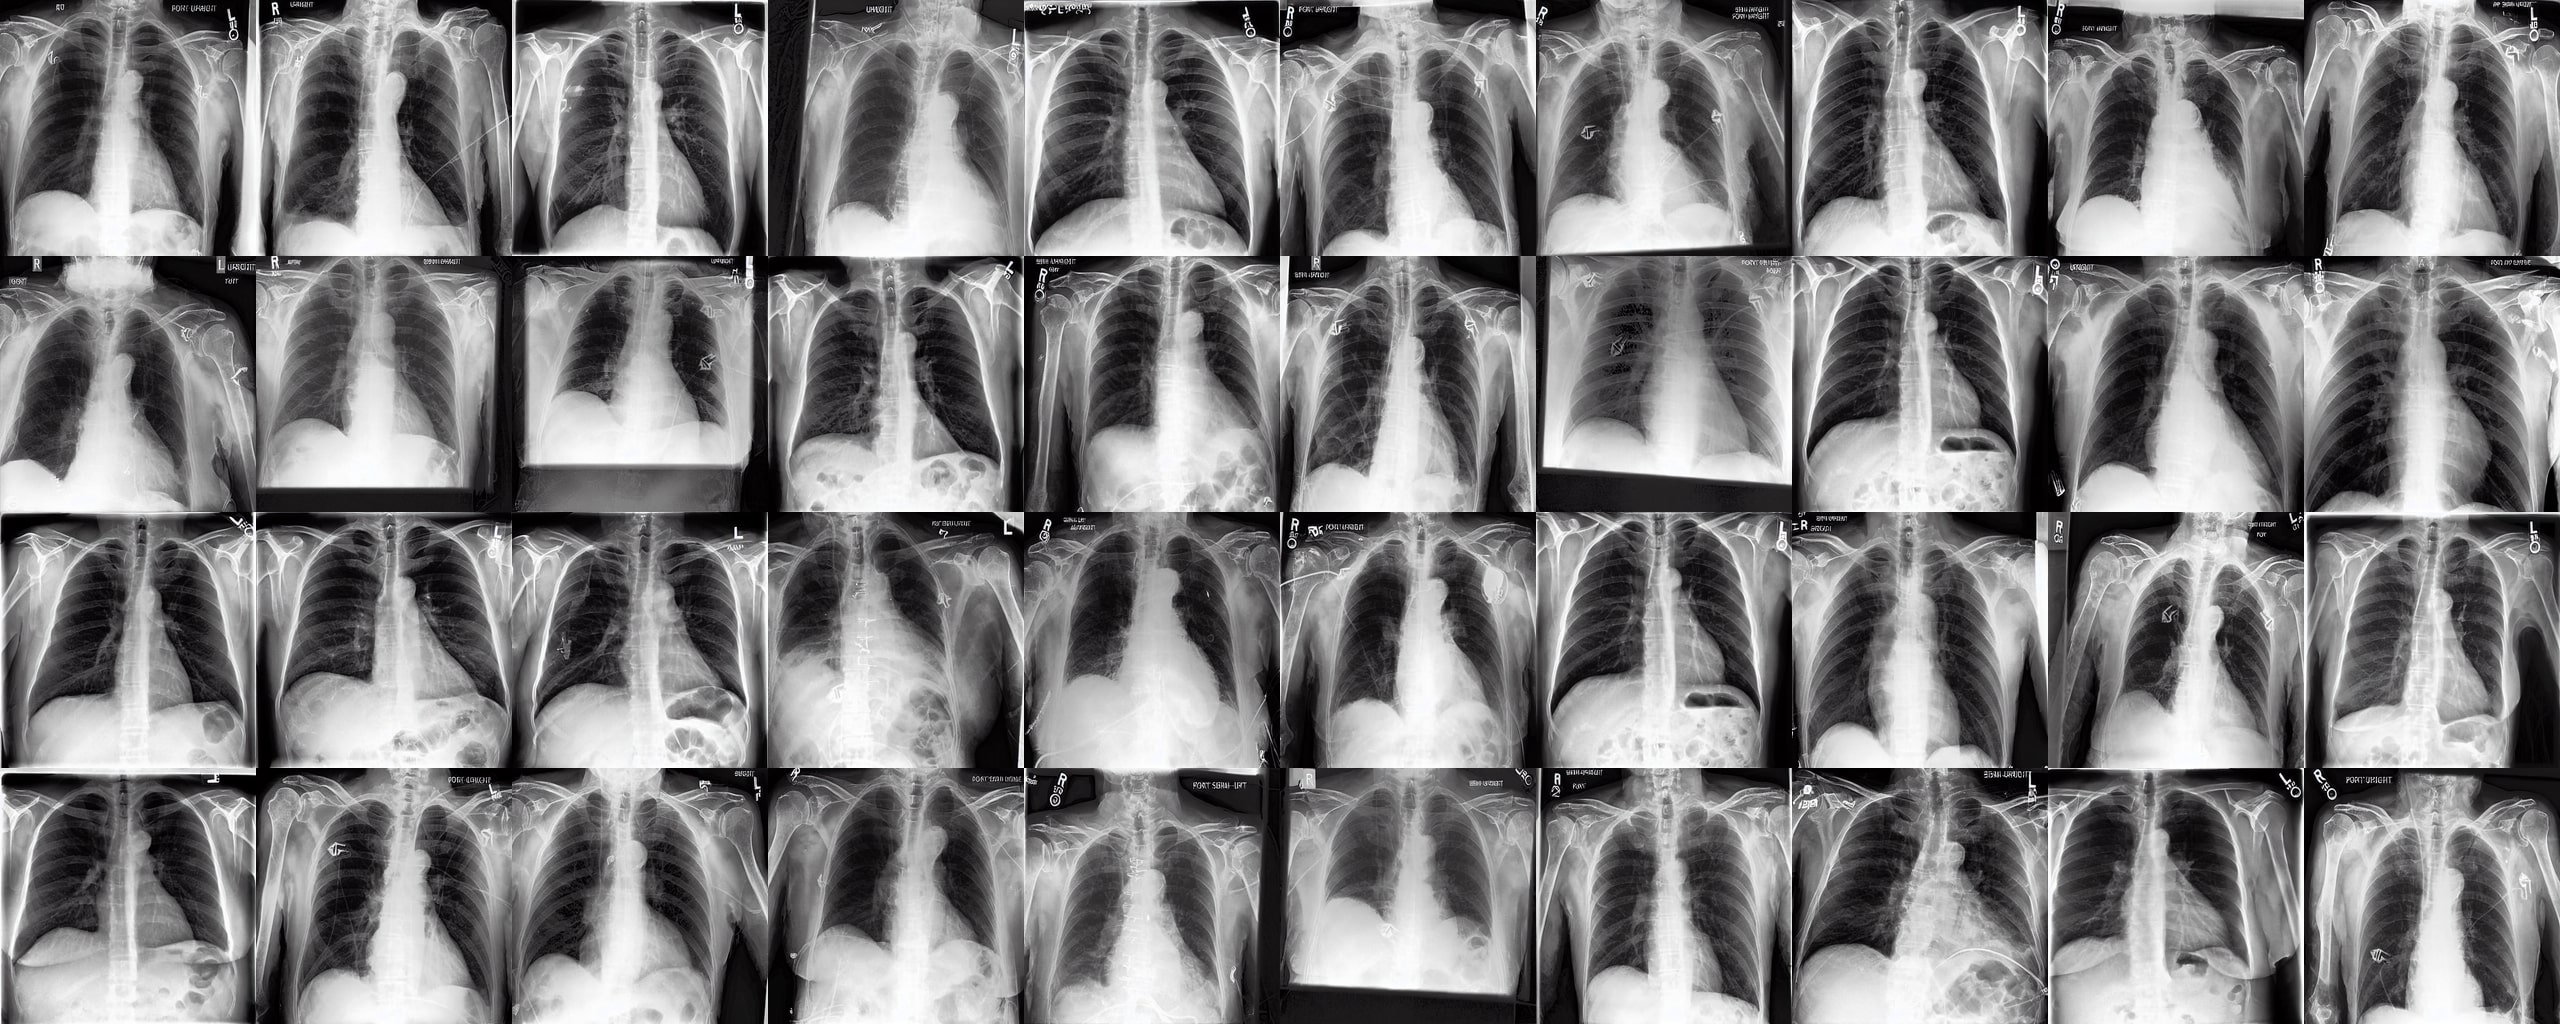

Chest X-rays We use the CheXpert dataset 10.1609/aaai.v33i01.3301590 , which contains 170k training images. This dataset contains diversity in medical devices (such as chest tubes and wires), diseases (such as pneumonia and pleural-effusion) and anatomical details. We implement Rainbow on top of frozen parameters of a finetuned Stable Diffusion v1.5 (SD1.5) by previous work kumar2025prism for chest X-ray data. We generate 2D chest X-ray images based on text prompt conditions, e.g., "Chest X-ray showing Support Devices". In addition to the finetuned SD1.5, we include RadEdit perez2024radedit , a model trained from scratch on multiple chest radiology data such as CheXpert irvin2019chexpert , MIMIC-CXR johnson2019mimic , and NIH-CXR wang2017chestxray data for image editing tasks (more details at Appendix D.3), in the result comparison. Rainbow’s graph generator module includes , , and .

Chest X-rays Figure 4b quantifies generations by Rainbow and baselines using FID and VS. Rainbow achieves a higher VS, indicating greater diversity than the finetuned SD model, while also improving image quality with a lower FID score. Both Rainbow and SD outperform the RadEdit. Figure 6 provides a qualitative comparison, images are generated using the prompt "Chest X-ray showing support devices", where Rainbow generates a more diverse set of medical devices, such as pacemakers, in all generations, while baselines do not show any devices in some images. All models achieve similar CLIP scores of . Additional results including generations, Figure 22 and numeric results, Table 4, are outlined in Appendix E.